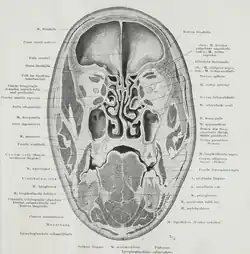

Des Weiteren kann – nach Fritz Frohse und Max Fränkel (1908) – ein Fettkörper oberhalb des Schulterblattes („Corpus adiposum suprascapulare“) beschrieben werden. Dieser sehr ausgedehnte Fettkörper liegt im hinteren Halsdreieck zwischen bzw. unter Sternocleidomastoideus, Clavicula, Trapezius sowie Levator scapulae.[3] Eine bildliche Darstellung (jedoch ohne Bezeichnung) findet sich u. a. in dem Anatomie-Atlas von Woerdemann (1948).